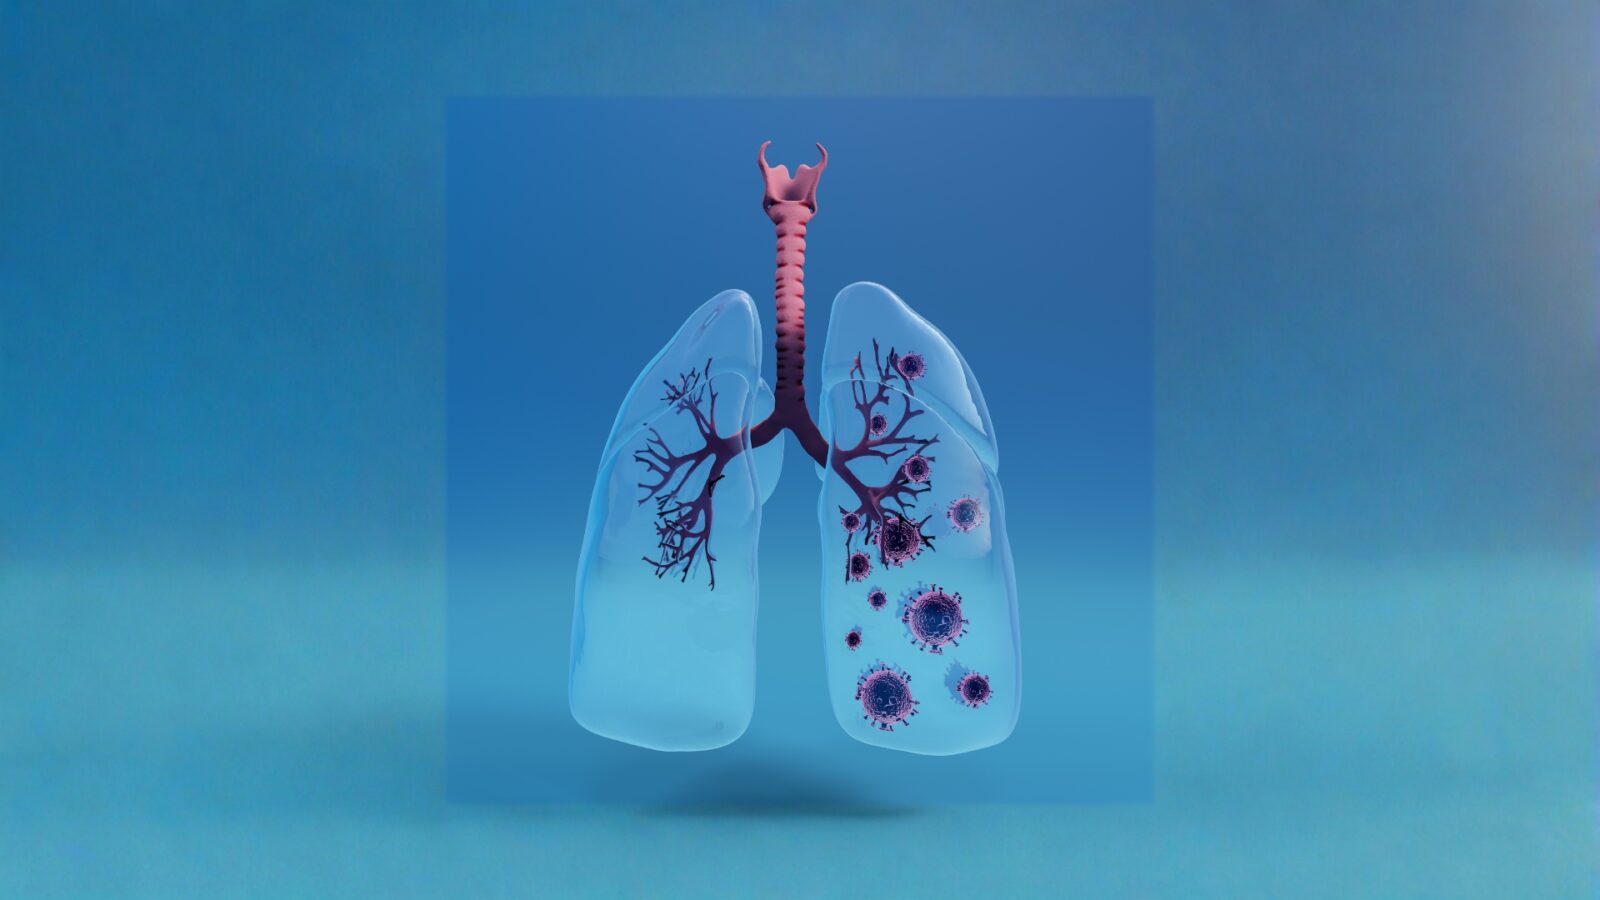

Bronkus adalah bagian penting dalam sistem pernapasan manusia yang sering dibahas saat seseorang mengalami batuk, sesak, atau infeksi saluran napas. Meski ukurannya tidak sebesar paru paru, peran bronkus sangat vital karena menjadi jalur utama udara menuju paru paru.

Apa Itu Bronkus

Bronkus adalah dua saluran utama yang bercabang dari trakea menuju paru paru kanan dan kiri. Setelah masuk ke paru paru, bronkus akan bercabang lagi menjadi saluran yang lebih kecil.

Cabang cabang kecil itu disebut bronkiolus. Dari bronkiolus, udara akan menuju alveolus, yaitu kantung udara tempat pertukaran oksigen dan karbon dioksida.

Letak Bronkus dalam Tubuh

Bronkus berada di rongga dada dan terhubung langsung dengan trakea. Setelah trakea bercabang, terbentuk bronkus kanan dan bronkus kiri.

Bronkus kanan biasanya lebih pendek dan lebih lebar dibanding bronkus kiri. Karena bentuk itu, benda asing yang terhirup lebih sering masuk ke bronkus kanan.

Bronkus kiri sedikit lebih sempit karena harus menyesuaikan ruang jantung. Walau begitu, keduanya tetap memiliki fungsi utama yang sama.

Gangguan yang Sering Menyerang Bronkus

Bronkitis

Bronkitis adalah peradangan pada bronkus yang sering menyebabkan batuk berdahak, dada tidak nyaman, dan napas berat.

Bronkitis akut umumnya muncul setelah infeksi virus. Sementara bronkitis kronis sering terkait kebiasaan merokok atau paparan polusi lama.

Asma

Pada asma, bronkus menjadi sensitif dan mudah menyempit. Gejalanya berupa mengi, sesak, batuk malam, dan dada terasa ketat.

Infeksi Saluran Napas

Bakteri atau virus dapat mengganggu bronkus. Saat infeksi terjadi, tubuh biasanya merespons dengan batuk dan peningkatan lendir.

Penyakit Paru Obstruktif Kronis

Kondisi ini membuat aliran udara terhambat secara menahun. Bronkus sering mengalami peradangan dan produksi lendir berlebih.